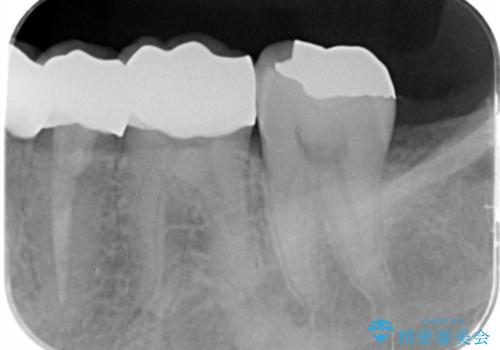

- 過去に治療したゴールドの詰め物が取れて来院。取れたのは2回目だそうです。レントゲンでは適合が良いので再装着可能だったが、

もう取れたくないとの事だったので被せ物のご案内をしました。ゴールドの被せ物の希望だったのでゴールドクラウンでの治療になりました。

適合の良いゴールドクラウンが入りました。

ゴールドは適合が良く、割れる心配もありません。